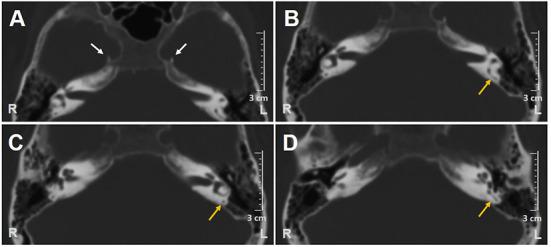

Vestibular neuritis (VN) mostly involves the superior vestibular nerve. Isolated inferior vestibular neuritis (IVN) has been more rarely described. The diagnosis of IVN is based on an abnormal head impulse test (HIT) for the posterior semicircular canal (PSC), pathological cervical vestibular-evoked myogenic potentials (C-VEMPs), and spontaneous downbeat nystagmus consistent with acute functional loss of inner ear sensors lying within the inferior part of the labyrinth. HIT for both lateral and superior semicircular canals is normal, as are ocular VEMPs and bithermal caloric irrigations. The etiology of IVN is debated since peripheral acute vestibular loss with a similar lesion pattern can often be associated with ipsilesional sudden hearing loss (HL). Viral inflammation of vestibular nerves is considered the most likely cause, although reports suggest that VN usually spares the inferior division. On the other hand, an ischemic lesion involving the terminal branches of the common cochlear artery has been hypothesized in cases with concurrent HL. Debated is also the lesion site in the case of IVN without HL since different instrumental patterns have been documented. Either isolated posterior ampullary nerve involvement presenting with selective PSC functional loss on video-HIT, or only saccular lesion with isolated ipsilesional C-VEMPs impairment, or inferior vestibular nerve damage (including both saccular and posterior ampullary afferents) exhibiting an impairment of both C-VEMPs and PSC-HIT. We report an interesting case of a patient with an acute vestibular loss consistent with IVN without HL who developed a PSC ossification on follow-up, questioning the viral origin of the lesion and rather orienting toward an occlusion of the posterior vestibular artery. To the best of our knowledge, this is the first report of PSC ossification after a clinical picture consistent with IVN.

前庭神经炎(VN)大多累及上前庭神经。孤立性下前庭神经炎(IVN)的描述则较为少见。IVN的诊断基于后半规管(PSC)的头部脉冲试验(HIT)异常、病理性颈前庭诱发肌源性电位(C-VEMP)以及与内耳迷路下部的内耳感受器急性功能丧失相符的自发性下跳性眼球震颤。外半规管和上半规管的HIT均正常,眼VEMP和冷热试验也正常。IVN的病因存在争议,因为具有相似病变模式的外周急性前庭功能丧失通常与同侧突发性听力损失(HL)有关。尽管有报告表明VN通常不累及下部分支,但前庭神经的病毒感染仍被认为是最可能的原因。另一方面,在并发HL的病例中,有人推测是涉及共同耳蜗动脉终末分支的缺血性病变。对于无HL的IVN病例,病变部位也存在争议,因为已记录到不同的检查模式。要么是孤立的后壶腹神经受累,视频HIT显示选择性PSC功能丧失,要么只是球囊病变伴孤立的同侧C-VEMP损害,要么是下前庭神经损伤(包括球囊和后壶腹传入神经),表现为C-VEMP和PSC-HIT均受损。我们报告了一例有趣的病例,一名患者出现与IVN相符的急性前庭功能丧失且无HL,随访时出现PSC骨化,这对病变的病毒起源提出了质疑,而更倾向于后前庭动脉闭塞。据我们所知,这是第一例临床表现与IVN相符后出现PSC骨化的报告。